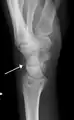

Triquetral fracture indicated by the white arrow. Triquetral fracture indicated by the white arrow.

Triquetral fracture as seen on lateral view of a radiograph. Triquetral fracture as seen on lateral view of a radiograph.

Triquetral fractures can occur due to forceful flexion of the wrist, causing an avulsion of the dorsal aspect of the bone that is often hidden on anterior radiographs, but can be seen as a tiny bone fragment on lateral views.